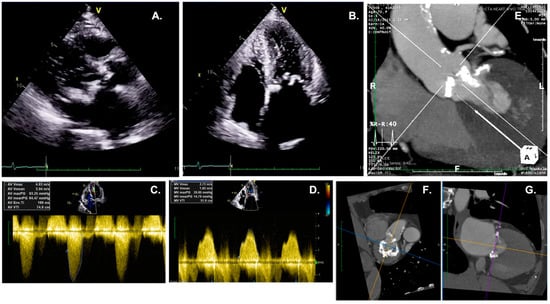

3.1. Role of Echocardiography

3.3. Role of CT